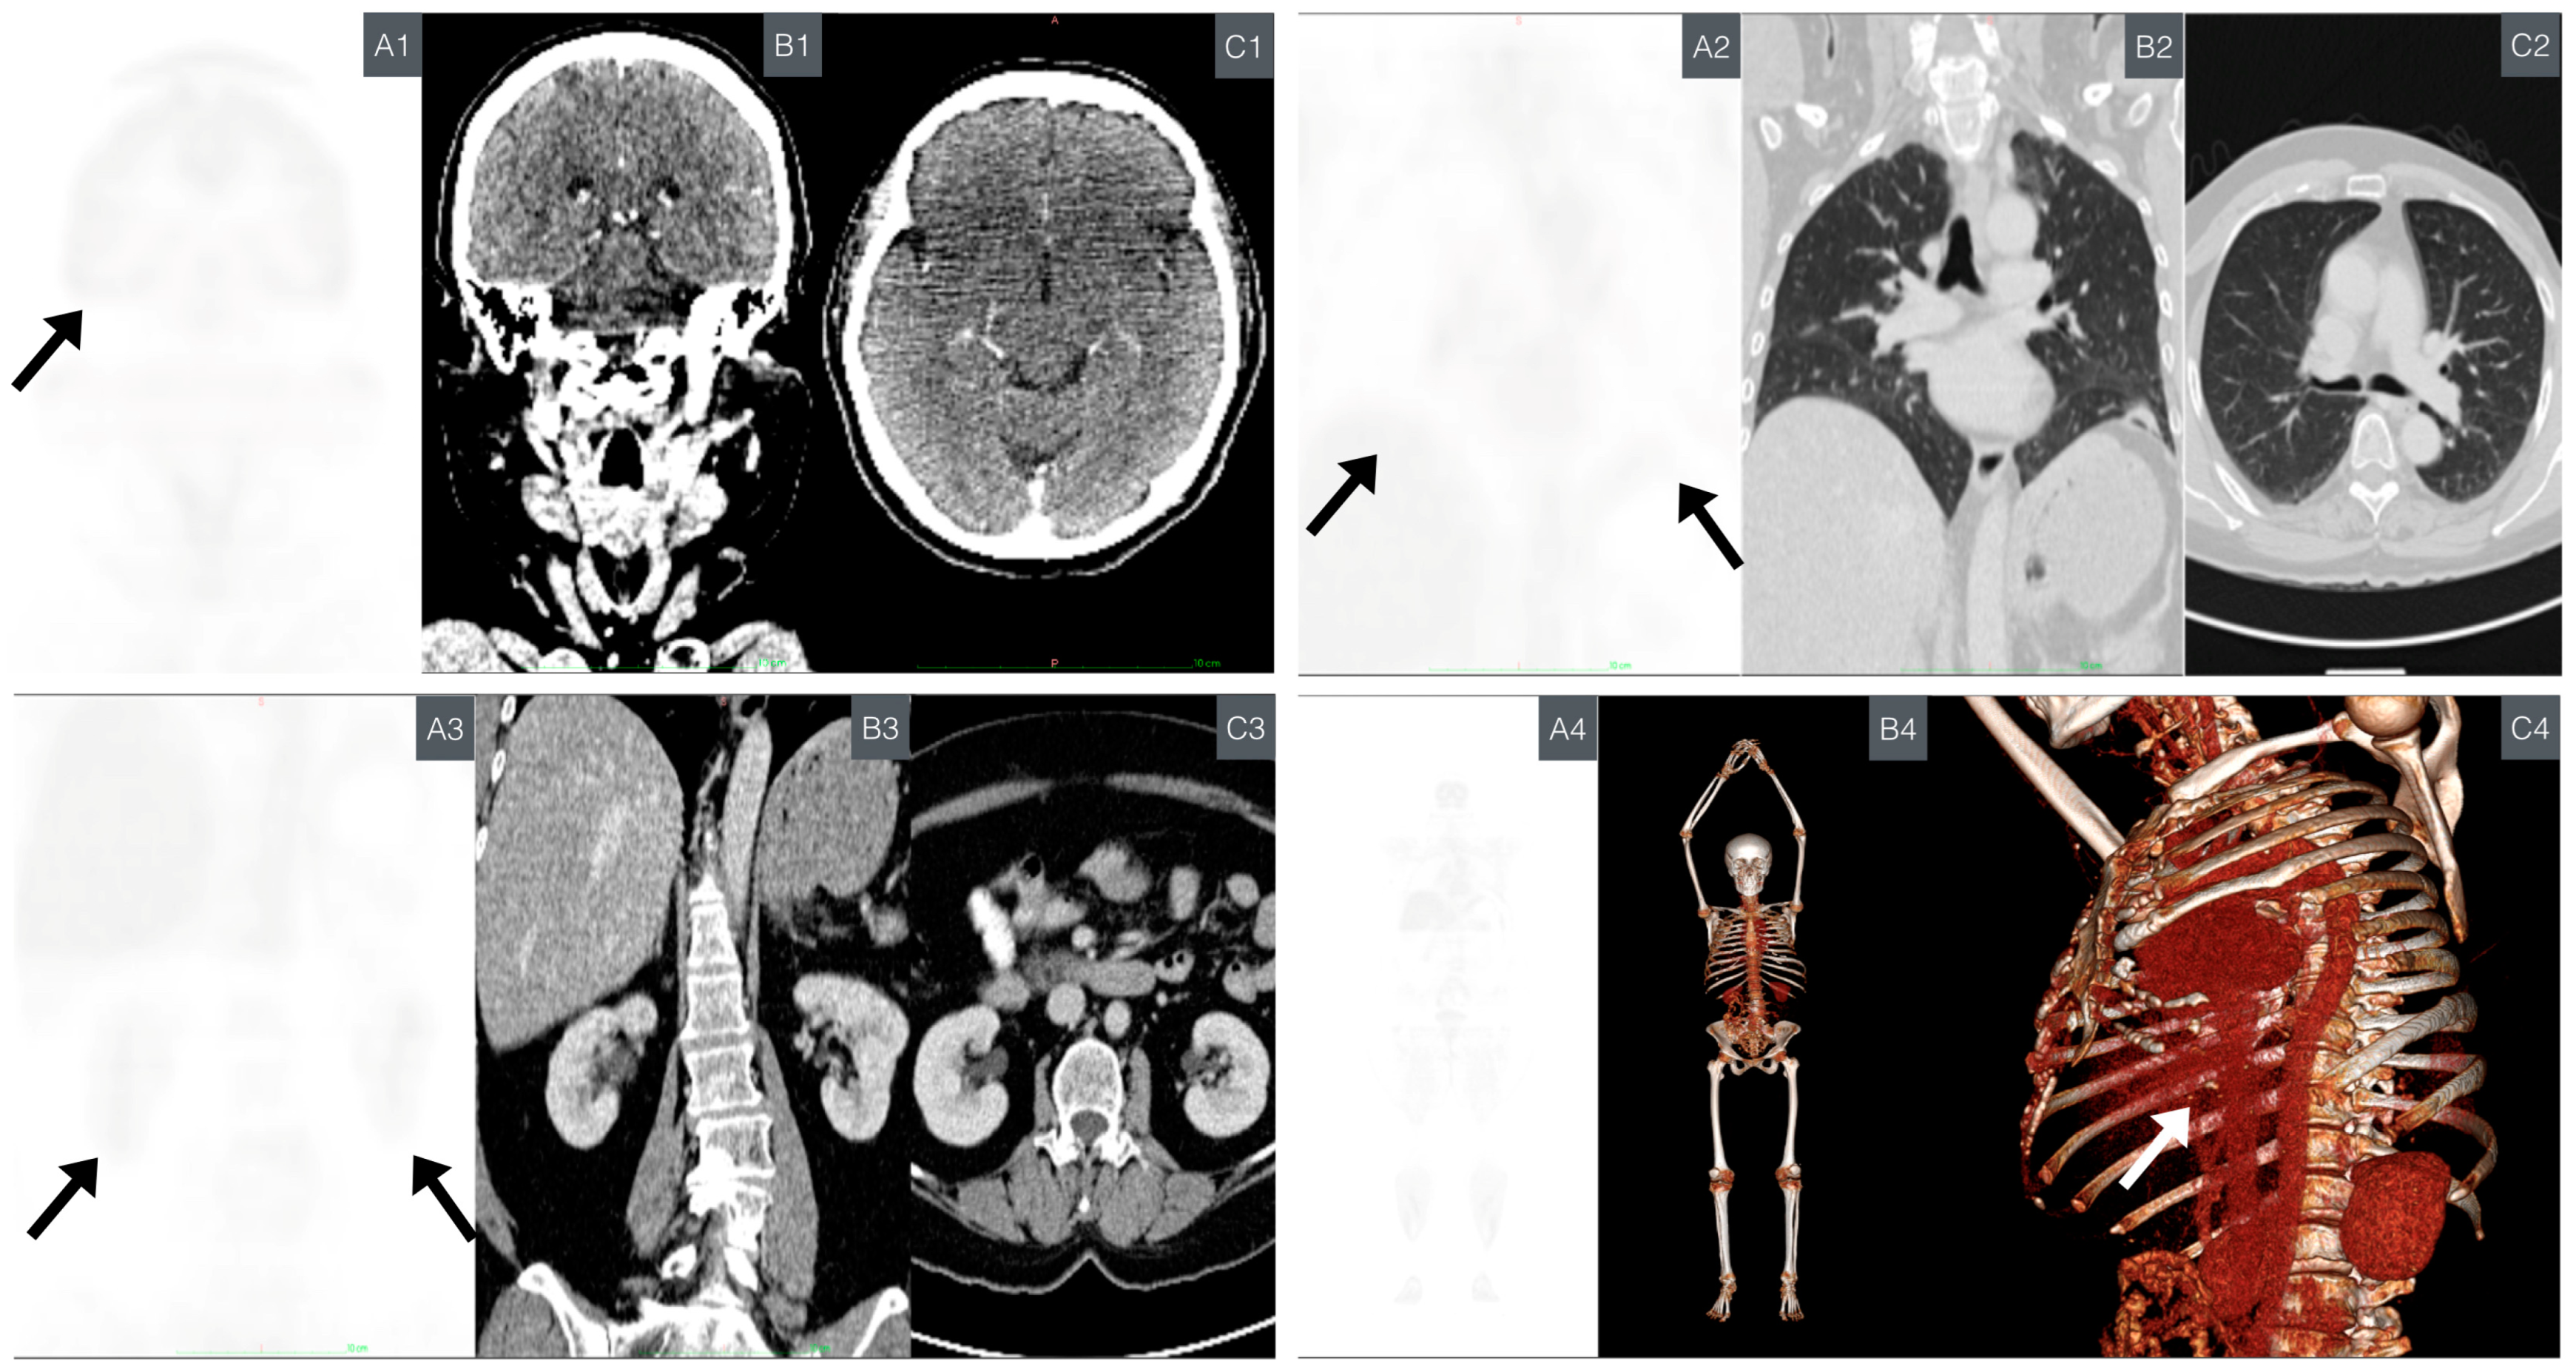

2.8. Full Body PET/CT

3.5. PET/CT Follow-Up

- Left rib region increased inflammatory metabolism: metabolic activity was observed in the corresponding area to the resection site with mesh placement. The SUVmax value was 2.8, falling within the expected and favorable prognostic range (<10.2 SUVmax) [73].

- Lung base subsegmental atelectasis: subsegmental atelectasis was noted in lung bases, along with a nodule in the lower lingula. The SUVmax for the nodule was 0.8, which is below the predictive malignancy cutoff value (SUVmax > 2.5) [74].